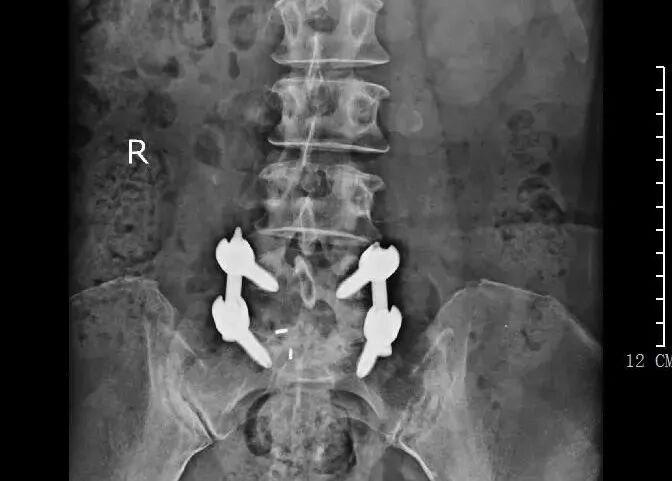

術(shù)后內(nèi)固定情況